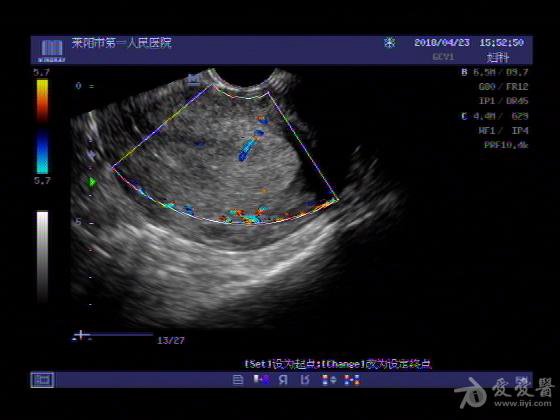

女,48岁,月经量多,两个月,一年前出现过类似现象,刮宫吃药后缓解。

超声可见:子宫内膜显著增厚,后肌壁内膜可见范围约3.27X0.90CM低回声区,CDFI显示较丰富线样血流,宫底宫腔内见类**状低回声结节。前肌壁见多发类圆形低回声结节。

超声提示:子宫内膜增厚(建议刮宫病理),子宫多发肌瘤

病理结果:内膜增生